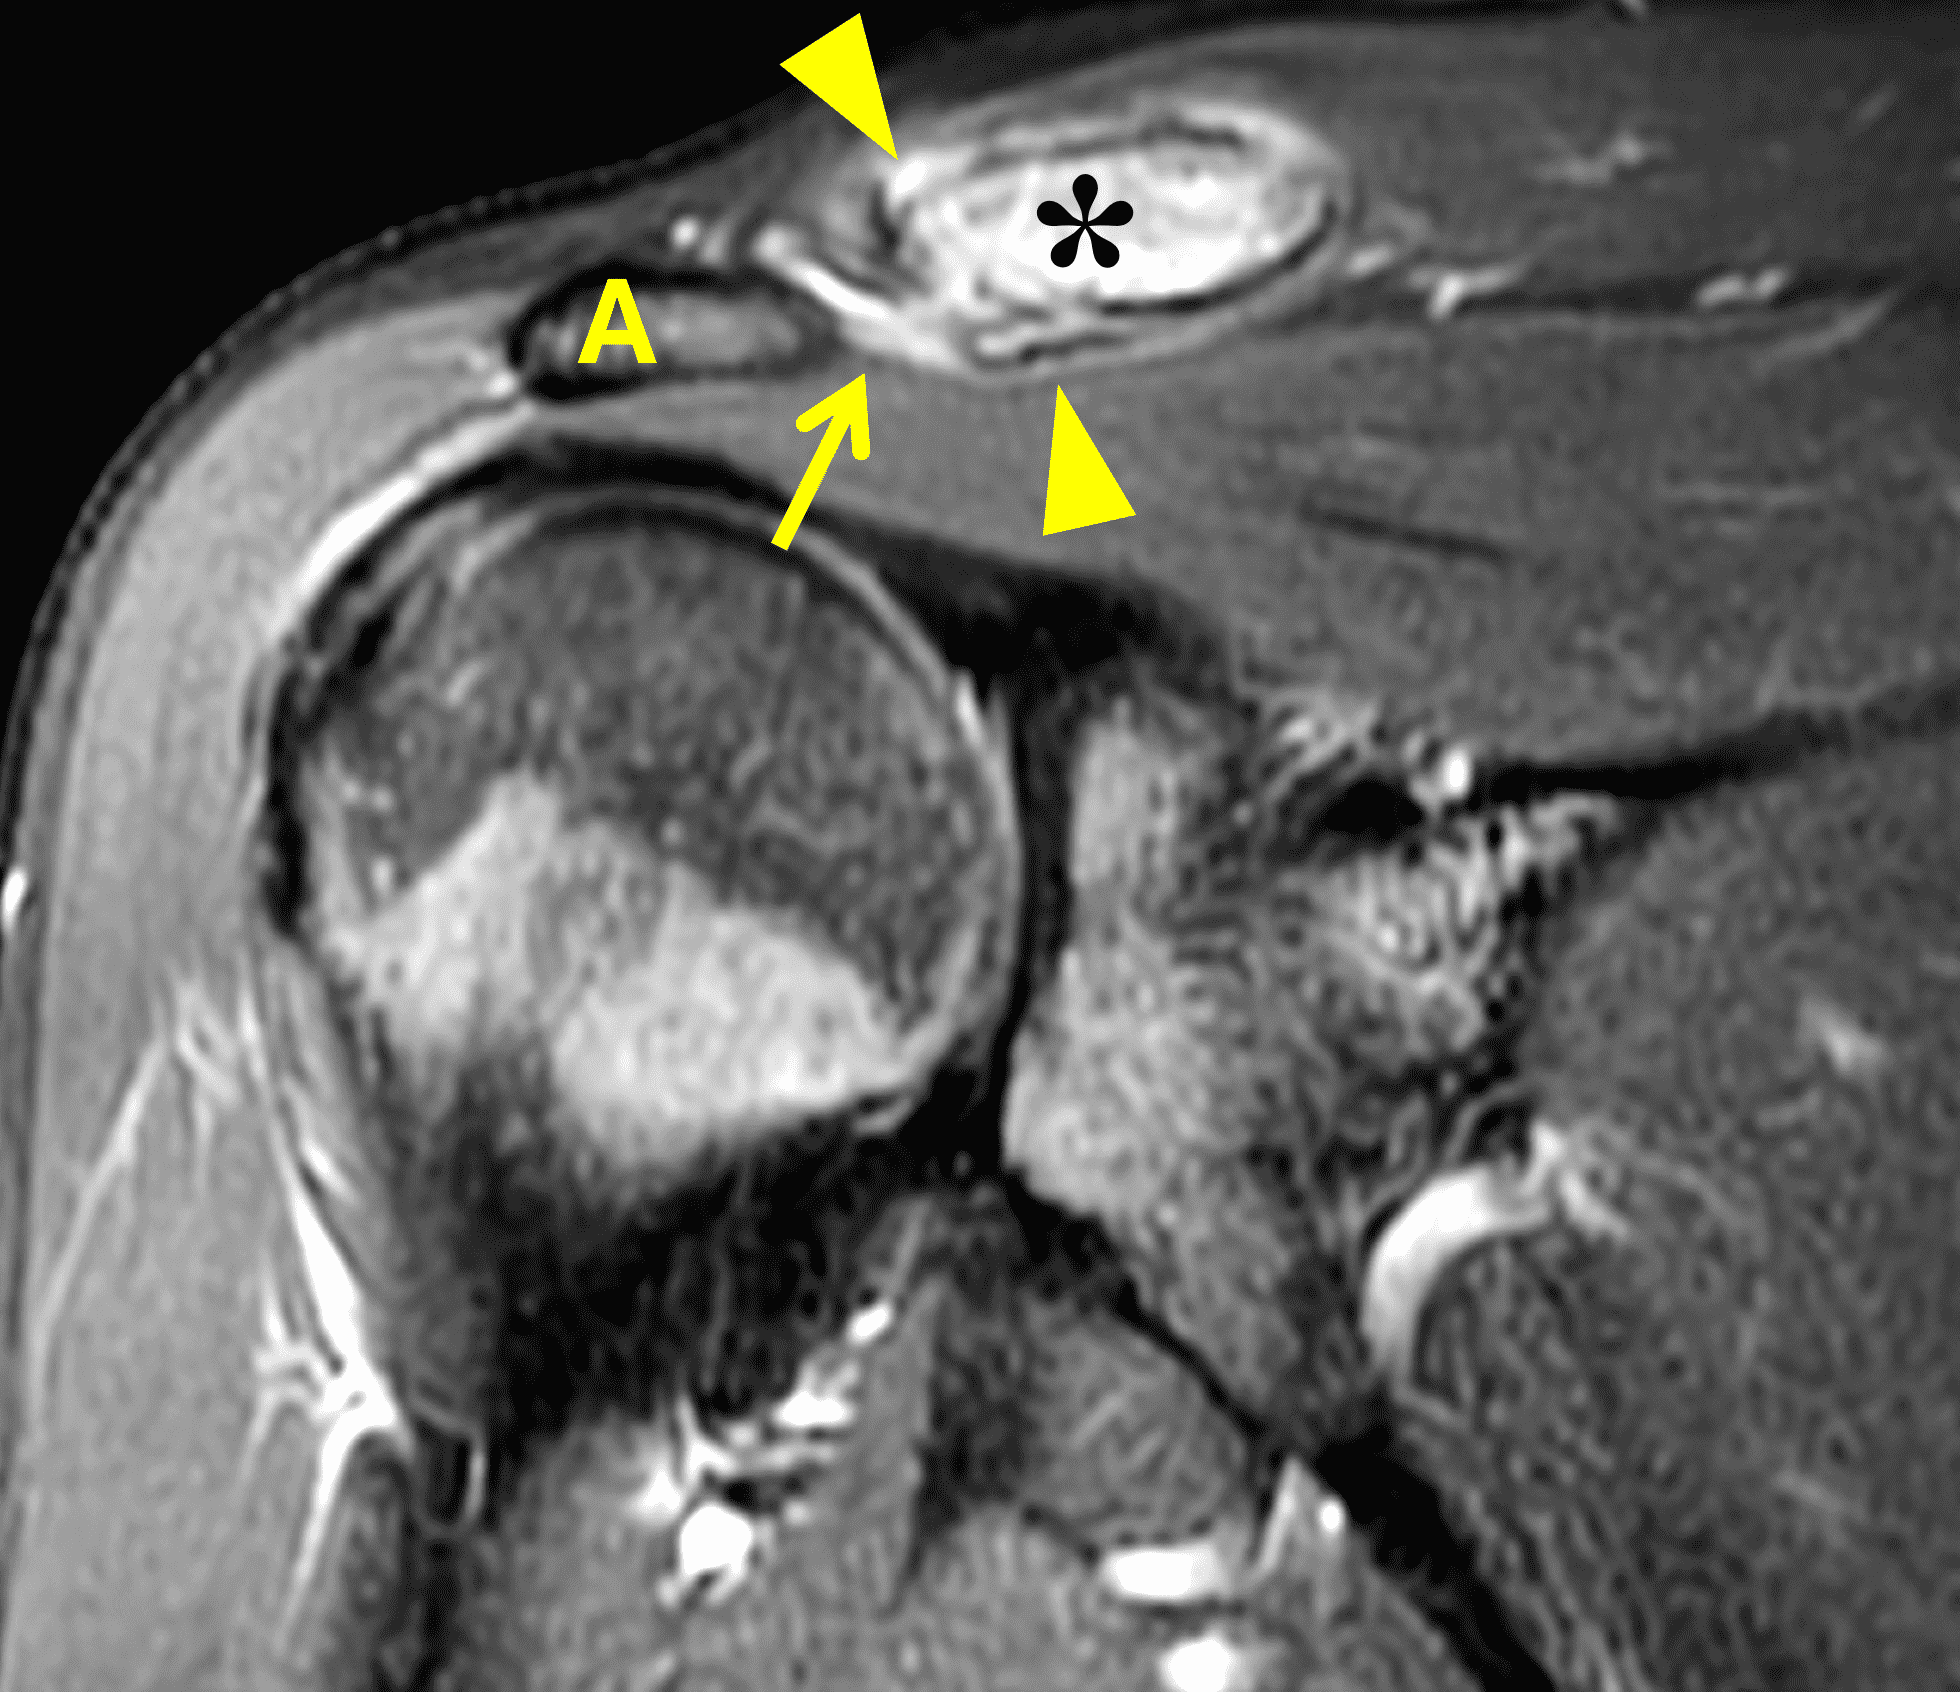

A 49-year-old male, avid weightlifter complains of chronic pain along the superior aspect of his right shoulder. He denies acute trauma. An AP radiograph (Figure 1A), as well as oblique coronal SPAIR (Figure 1B), axial fat-suppressed fluid sensitive (Figure 1C), and oblique sagittal T2-weighted images (Figure 1D) are shown. What are the findings? What is your diagnosis?

MRI: MRI is the primary imaging modality used for the diagnosis of DCO and identifies relevant findings earlier than radiographs or CT.  To differentiate DCO from similar conditions, it is important to identify underlying findings that are isolated to or more pronounced in the distal clavicle compared to other structures.  Osseous changes along both the acromial and distal clavicular margins of the joint often point to a different diagnosis.2

The principle MRI finding of DCO is distal clavicular marrow edema and surrounding inflammation on fluid-sensitive pulse sequences, especially with fat suppression (Figures 3 and 4).2, 9 Marrow changes can occur in patients with normal radiographs,10 in which case a term like “stress/overuse related marrow edema,” might be preferable to “osteolysis.” On MRI, more severe cases may show erosions or cysts in the distal clavicle and loss of the subchondral bone plate in addition to more pronounced marrow and soft tissue edema. A band of low signal paralleling the distal bone end may be present, suggesting a stress fracture line (Figure 5).8 However, a similar appearance can be due to the sclerotic rim surrounding distal clavicle cysts or small erosions (Figure 6). A small effusion or mild synovitis is often present in the AC joint.  Soft tissue edema within and surrounding the AC joint capsule and distal clavicular periosteum may be visible (Figure 3).  Some patients may also show marrow edema (or even erosions) in the anterior acromion, but the changes are typically more severe in the distal clavicle (Figures 5 and 7).2

While isolated DCO does not produce osteophytes, it may occur in patients with pre-existing osteoarthritis; in these cases, the marrow edema is typically out of proportion to the osteophytosis. When DCO occurs following an acute traumatic event like an AC joint separation, the MRI findings of that condition (e.g., widening or subluxation of the joint, disruption of the coracoclavicular ligaments) may be evident (Figure 8).1 Osteolysis can also develop following fractures of the distal clavicle, due to post-traumatic resorption of small, comminuted fracture fragments. In these cases, residual deformity of the clavicle or the presence of the original fracture lines may be evident on imaging studies. Additionally, because resorption of the fracture fragments typically occurs during the chronic healing after inflammation has resolved, marrow and soft tissue edema may not be present on MRI when the distal clavicular bone loss is seen.